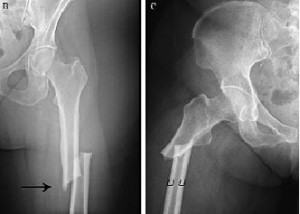

La rápida reversión del beneficio es una preocupación con el uso de denosumab. En este estudio, si la dosis de seguimiento de denosumab se atrasaba por más de 16 semanas la tasa de fracturas vertebrales aumentaba casi 4 veces en seis meses. Annals of Internal Medicine, 28 de julio de 2020.